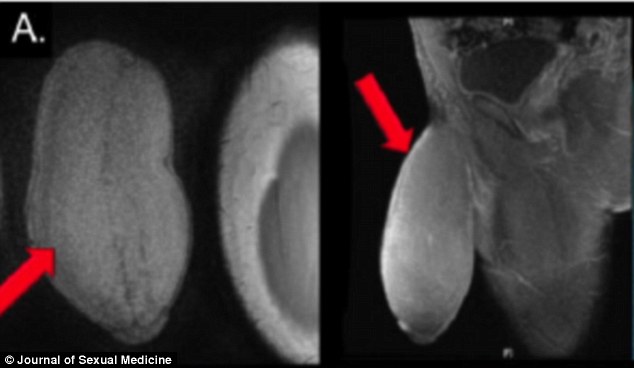

Il suo organo di riproduzione era enorme e soprattutto era più largo che lungo, una specie di palla da rugby: e così l’equipe di un ospedale in Florida è intervenuta (con successo) per eseguire il primo intervento di riduzione del pene su un ragazzo di 17 anni, la cui misura dell’organo, come riporta il Journal of Sex Medicine, era di 18 centimetri di lunghezza e 25 centimetri di circonferenza.

“La forma ricordava quella di un pallone da football”, ha commentato Rafael Carrion, il chirurgo urologo dell’Università della South Florida che ha operato il ragazzo, e che ha deciso di trattare il problema come solitamente si fa con la malattia di Peyronie, un’alterazione che colpisce i corpi cavernosi del pene.

Il giovane operato incontrava difficoltà anche solo nell’indossare pantaloni stretti o nell’avere rapporti sessuali e, in più, soffriva di attacchi di priapismo, una forma di erezione improvvisa che lasciava l’organo gonfio e deformato.

“Sembra il sogno di ogni uomo ma, sfortunatamente, nonostante la lunghezza e la durata generose, la circonferenza era esagerata, soprattutto nel mezzo”, ha commentato ancora Carrion: “Non gli sembrava vero – racconta infine il dottore – il mio paziente era tutto sorridente e completamente soddisfatto”.